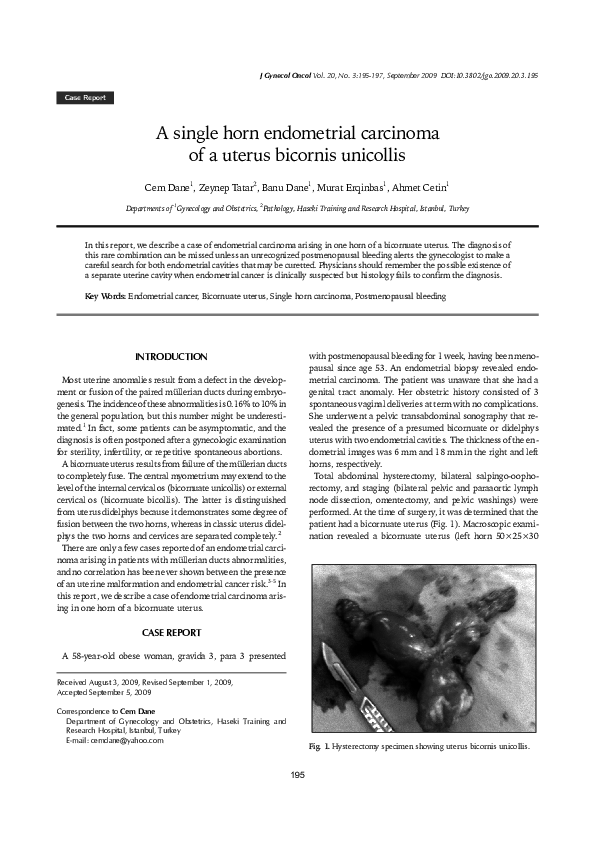

Single Horn Carcinoma . Gross examination revealed a bicornuate uterus (fig. A case report. by khaled. A single horn endometrial carcinoma of a uterus bicornis unicollis. In this report, we describe a case of endometrial carcinoma arising in one horn of a. Semantic scholar extracted view of endometrial carcinoma in a single horn of a bicornuate uterus: In conclusion, endometrial cancer arising in one horn of didelphys uterus is very rare. Each horn may be affected independently with. Cem dane, 1 zeynep tatar, 2 banu dane, 1 murat. 1a) (left horn 6.5×4×3.5 cm, right horn 7×4×3 cm) with a single cervix.

Gross examination revealed a bicornuate uterus (fig. Cem dane, 1 zeynep tatar, 2 banu dane, 1 murat. A case report. by khaled. In conclusion, endometrial cancer arising in one horn of didelphys uterus is very rare. Semantic scholar extracted view of endometrial carcinoma in a single horn of a bicornuate uterus: In this report, we describe a case of endometrial carcinoma arising in one horn of a. Each horn may be affected independently with. 1a) (left horn 6.5×4×3.5 cm, right horn 7×4×3 cm) with a single cervix. A single horn endometrial carcinoma of a uterus bicornis unicollis.